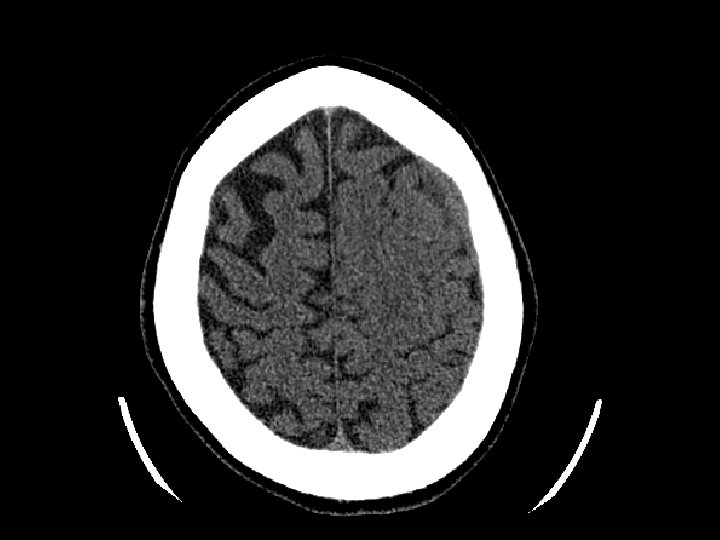

Concussion • Brief change in brain function usually with loss of consciousness/amnesia • Head CT often normal • Post-concussive syndrome: – Headache, confusion, difficulty concentrating, memory problems, nausea – May last hours to months • Treatment – Simple observation – Limit activity that may reinjure patient’s head • Avoid “repeat concussion”

Cerebral Contusion • Bruising to the brain • Most common traumatic finding on CT • Large contusions may have significant bleeding (hemorrhagic contusion or intracerebral hematoma), edema, or cause seizures • Location: Frontal and Temporal lobes – Due to irregularity of the skull base • Treatment: close observation

Subarrachnoid Hemorrhage (SAH) • SAH and contusion are most common injuries on CT after blunt trauma • CT: blood in the sulci and basal cisterns • Often associated with intracranial hematomas • Must consider that the SAH caused the trauma (spontaneous bleed and then fall) • Complications: – Arterial vasospasm: 2 -3 days after injury